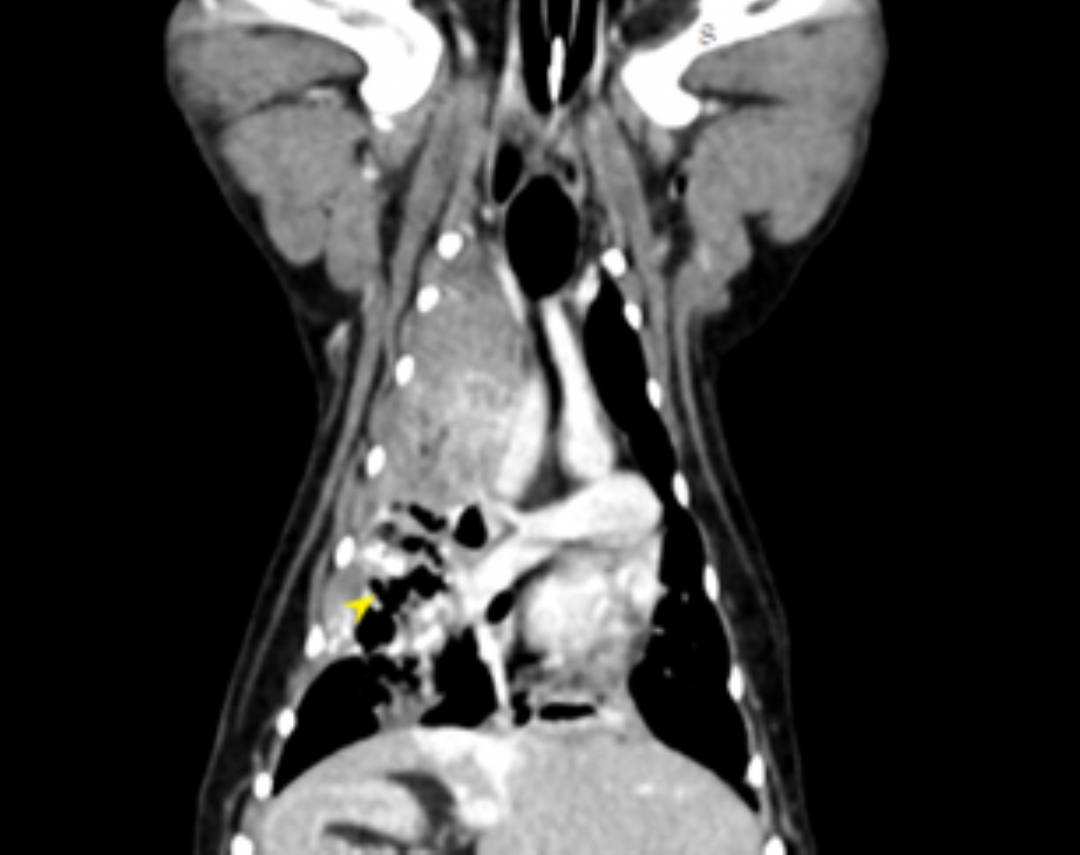

狗狗 肺臟腫瘤 Pulmonary carcinoma

持續數月的咳喘 他院懷疑心臟問題轉診來築心,經由電腦斷層掃描及胸腔採樣

確診為惡性腫瘤,由於腫瘤已經擴散不適合外科手術,主人最後決定使用化療延長壽命